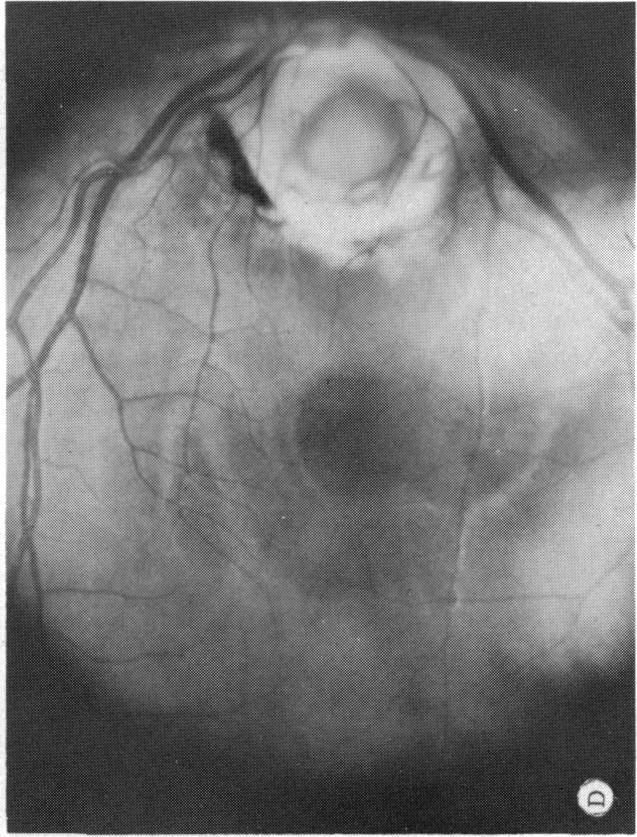

Six cases of congenital pit of the optic nervehead associated with posterior serous retinal detachment are presented. All were treated by photocoagulation along the disc margin in the area of retinal detachment. In five cases reattachment of the retina occurred, after the clinical development of a film chorioretinal adhesion at the disc margin, and appeared to be secondary to the treatment. The sixth case (Case 4), although treated, appeared to represent a spontaneous reattachment. This disorder, which frequently results in permanent decrease of central vision, affected the better, or only, eye in two of the six cases herein reported. Fluid, probably from the vitreous cavity, appears to gain access to the subretinal space via the pit. Reattachment in treated cases occurred only if an effective chorioretinal adhesion was created over the entire area of the fistulous detachment at the disc margin. Field defects after treatment appear to be secondary to either the optic pit itself or the longstanding retinal detachment, oftern accompanied by pigmentary degeneration and cystic macular degeneration, rather than juxtapapillary photocoagulation treatment.

本文报告6例先天性视神经乳头凹合并浆液性视网膜脱离。所有病例均采用视网膜脱离区域沿视盘边缘光凝治疗。5例视网膜脱离在视盘边缘形成脉络膜视网膜粘连后复位,似乎是治疗的继发结果。第6例(病例4)虽经治疗,但似乎是自发复位。这种疾病常导致中心视力永久性下降,在本文报告的6例中有2例影响了较好或仅有的一只眼。液体可能来自玻璃体腔,似乎通过视神经乳头凹进入视网膜下间隙。治疗病例中,只有在视盘边缘瘘管性脱离的整个区域形成有效的脉络膜视网膜粘连时,视网膜才会复位。治疗后的视野缺损似乎继发于视神经乳头凹本身或长期视网膜脱离,常伴有色素性变性和黄斑囊样变性,而非视盘旁光凝治疗。